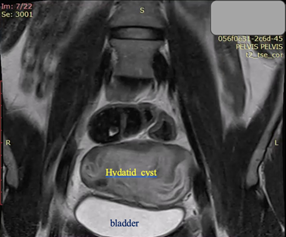

A 23-year-old asymptomatic female patient. During a routine gynecological examination, pelvic ultrasound identified a nonspecific tumor-like mass of solid consistency (Figures 1-3). The patient is sexually active and nulliparous. She has no history of abnormal menstrual bleeding or pelvic pain. Pelvic ultrasonography demonstrated a nonspecific tumor-like mass. The lesion was located in the vesicouterine space, anterior to the uterus (which was in anteversion and anteflexion with length 6.5 cm.) and posterior to the urinary bladder. The mass measured approximately 10 cm and had a predominantly solid component, with multilaminar hypoechoic bands within its capsule (Figures 1 and 4). Both ovaries were visualized and appeared normal on transvaginal ultrasonography (Figures 2 and 3). The pouch of Douglas is free of fluid.

Figure 5. Coronal T2-weighted MRI: The massive cystic formation displaces the bladder ventrally and alters the normal position of the uterus